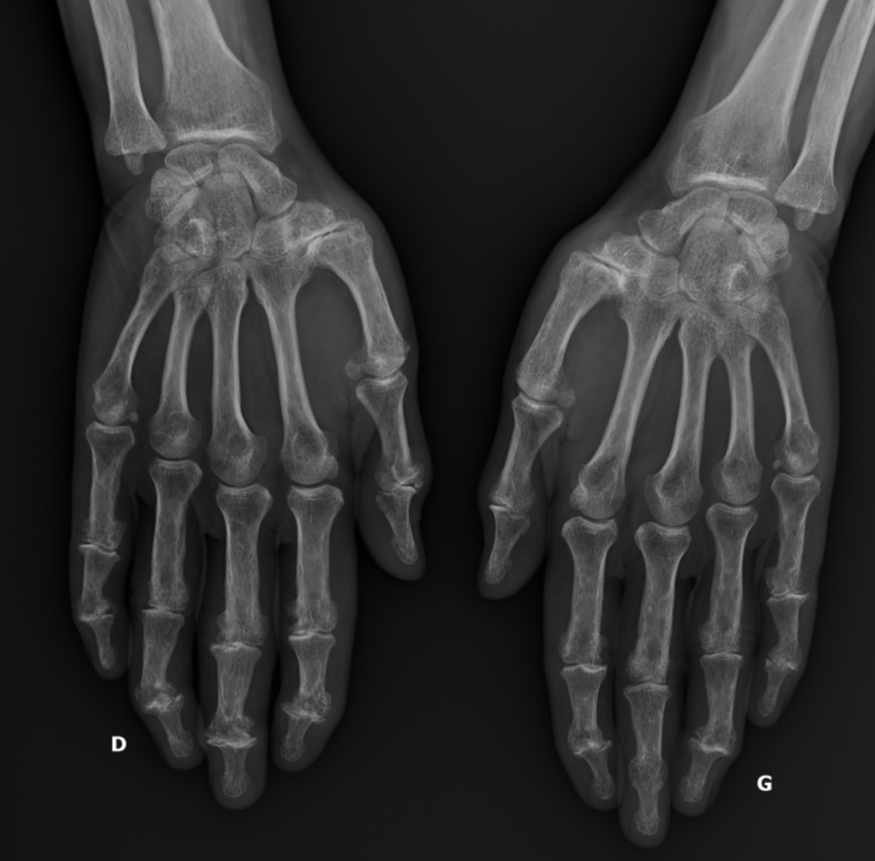

- Figure 2 rhizarthrose bilatérale